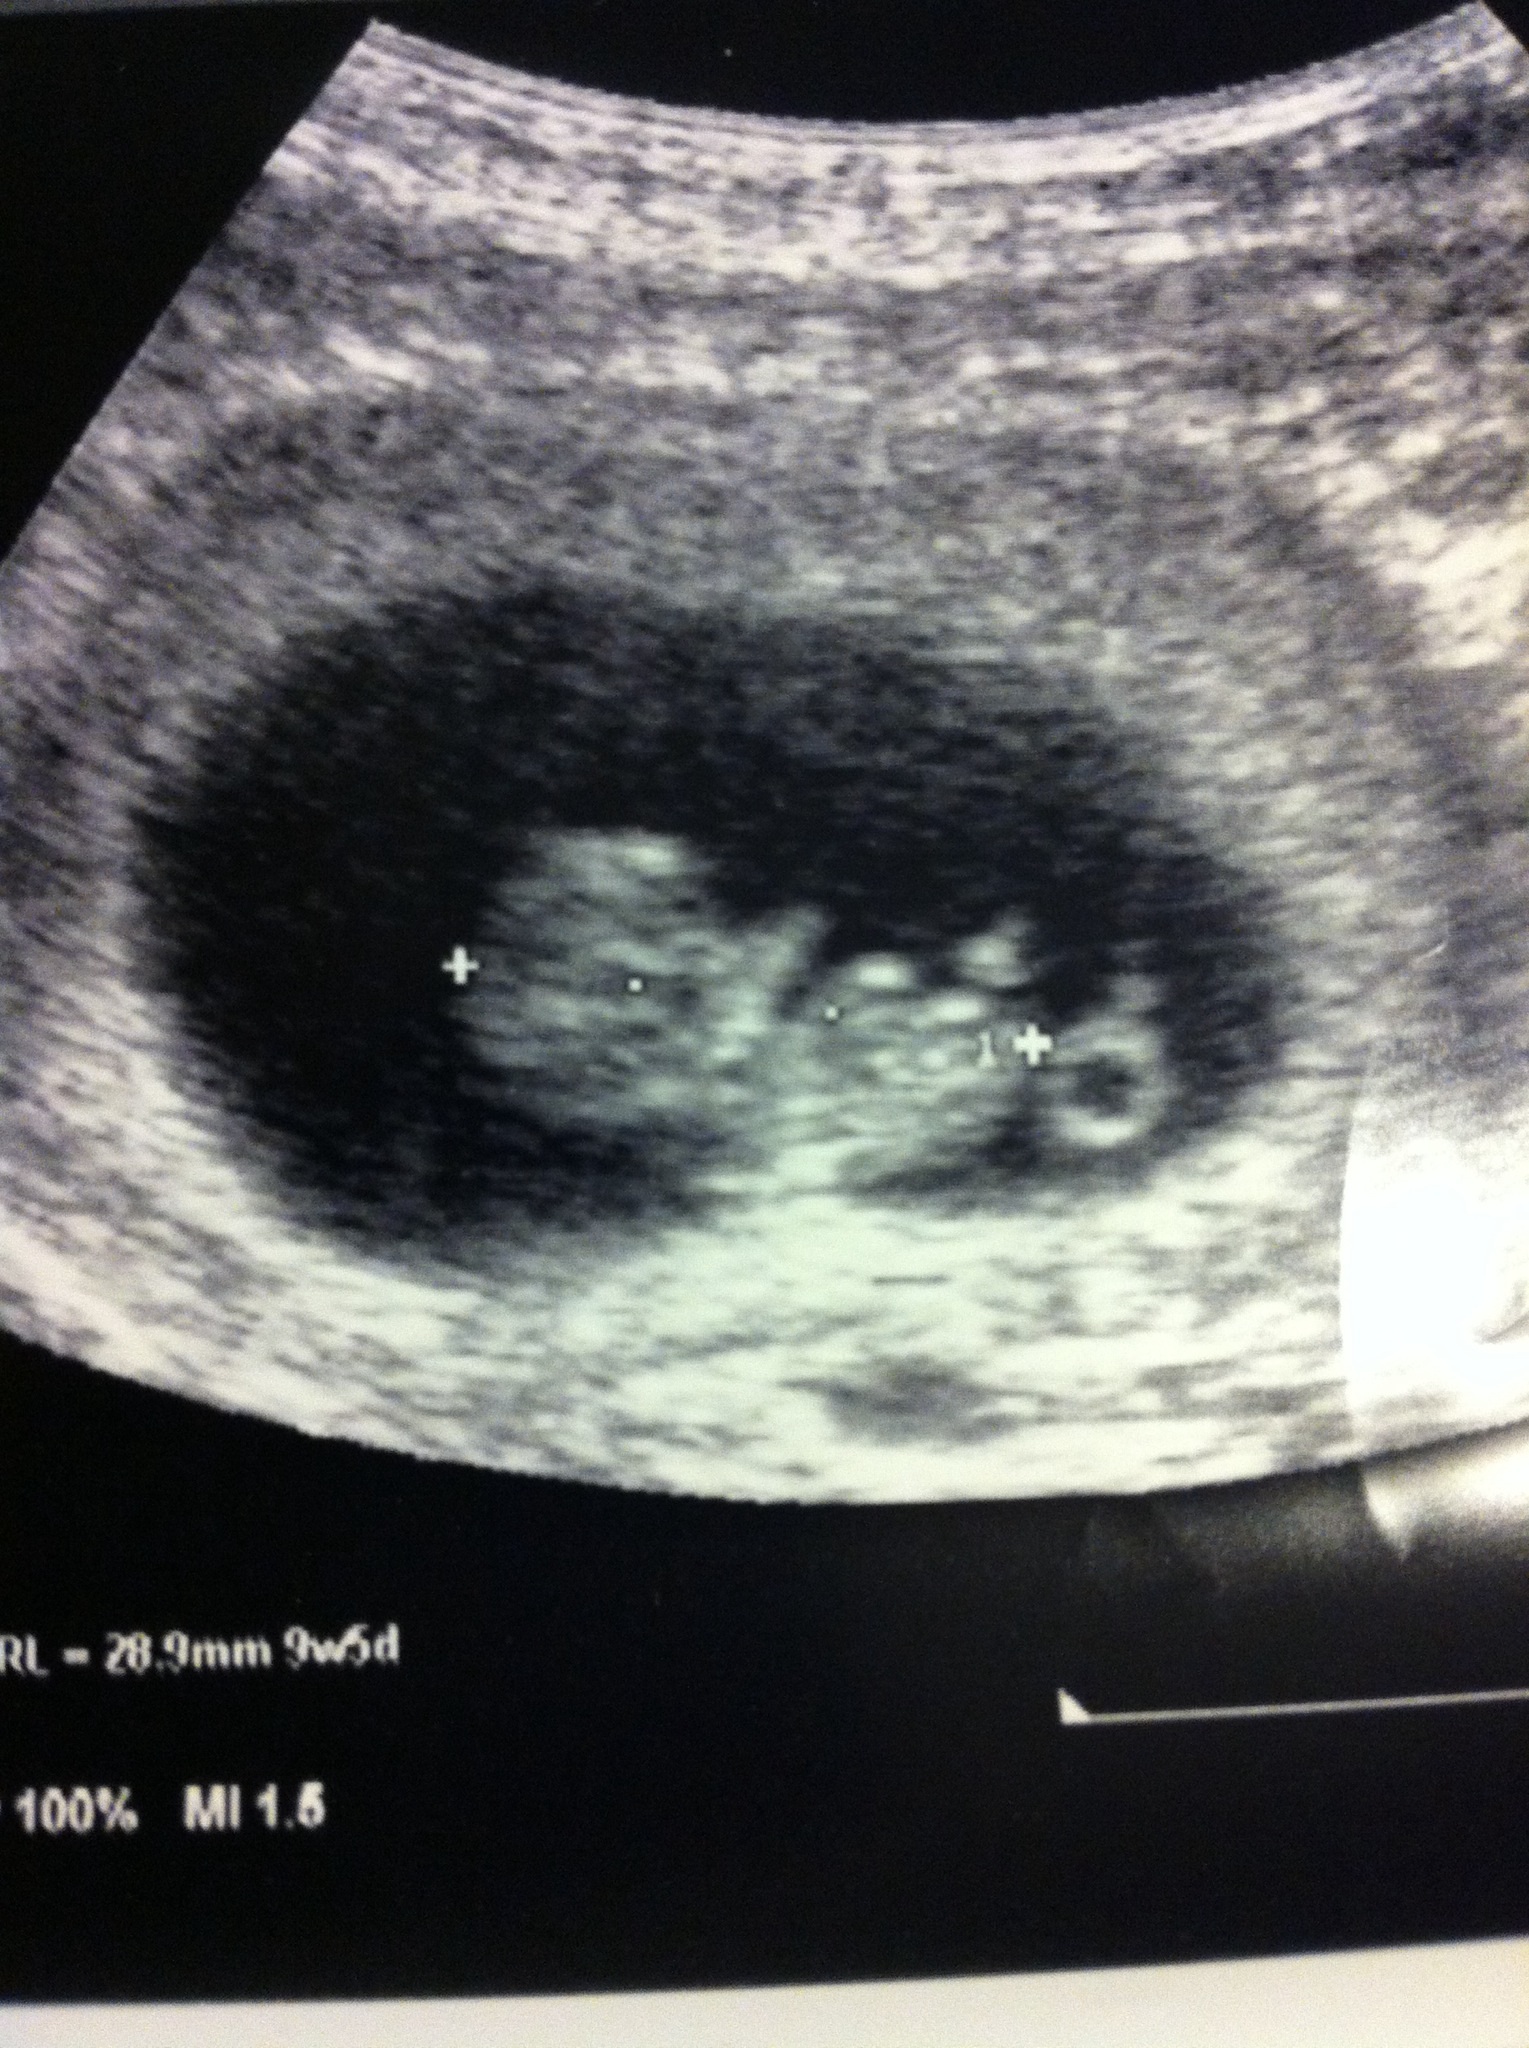

My first appt went well, US showed ahead of schedule at 9w5d (LMP date should have been 9w1d). HB around 160s. Lots of blood taken and a lecture about drinking more water. Next appt with MD in 1 month. It finally seems real now :)